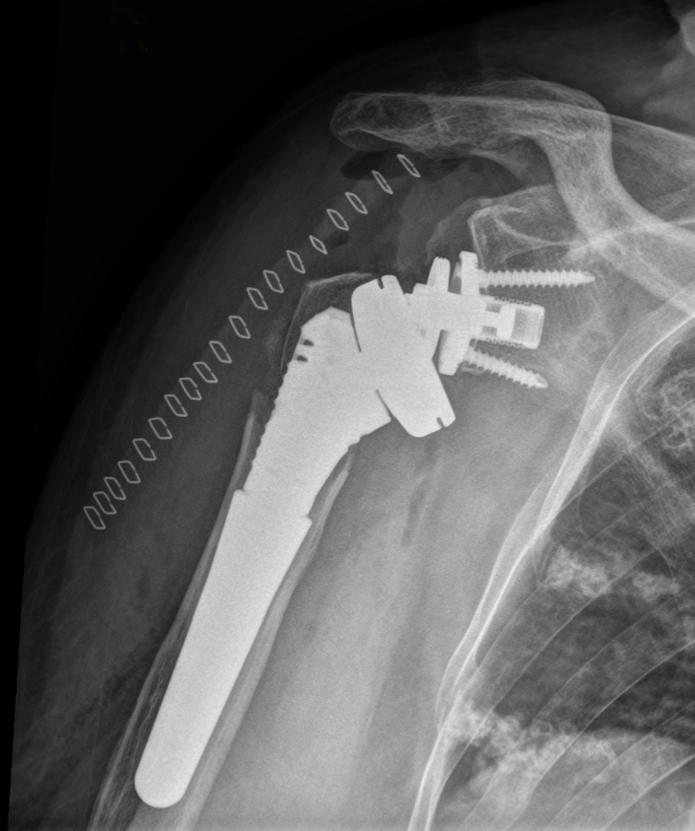

Post-op

Implantation of LINK Embrace using

- Proximal Body with cementless Distal Stem

- Neutral Reverse Tray, paired with CoCrMo Reverse Insert height -3 (extremely space saving)

- E-Dur Glenosphere (Vit. E infused UHMWPE) with 39 mm diameter in eccentric version

- Reverse Glenoid Baseplate, standard, with inferior and superior cortical locking screws

- Good stability

- Good soft tissue tension

- Excellent ROM, especially int./ ext. rotation and adduction